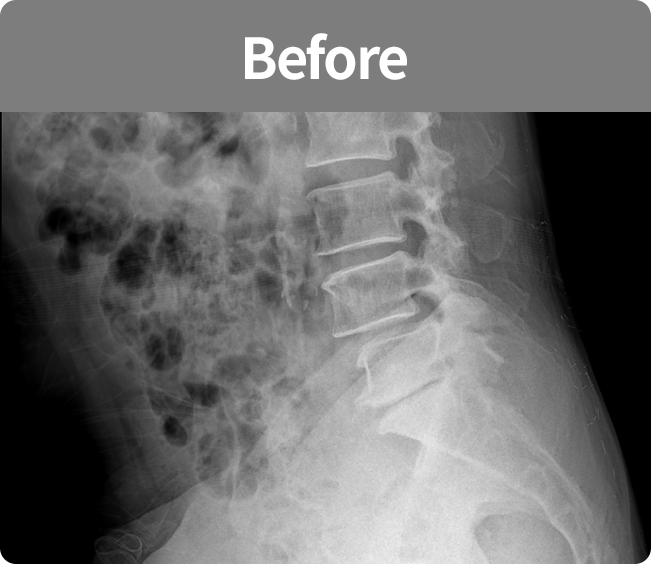

척추유합술

미세현미경을 통해 손상된 뼈와 인대조직을 제거하고 디스크의 역할을 해줄 인조 케이지를 삽입해

불안정한 척추체를 나사못으로 고정하는 수술 (척추 전방 골유합술, 척추 후방골유합술)